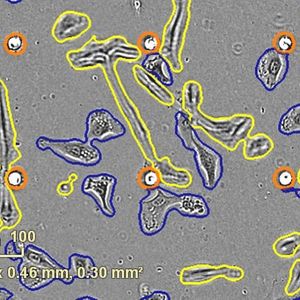

JUL 03, 2023CancerStem cells are valuable to a wide range of biomedical and pharmaceutical research applications because of their high sel ...